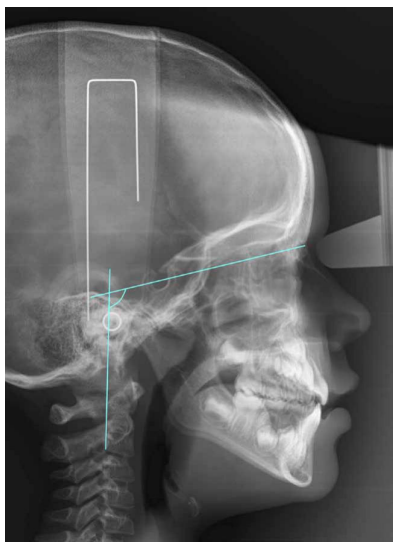

Relación entre los patrones de crecimiento facial y la maduración dental y esquelética en los pacientes en crecimiento

El objetivo de este trabajo es realizar una revisión bibliográfica para evaluar la posible relación entre los patrones de crecimiento facial con la maduración dental y esquelética en pacientes en crecimiento. La maduración dental y esquelética son dos indicadores que nos permiten establecer en qué momento del desarrollo se encuentra el paciente en crecimiento. Actualmente, para la valoración de la maduración esquelética se emplea la visualización de las vértebras cervicales en la radiografía lateral de cráneo, ya que es un método que permite disminuir la exposición radiológica del paciente que se encuentra en estudio ortodóncico, en comparación con la radiografía de muñeca,

la cual suponía la realización de una radiografía adicional. Para el análisis de la maduración dental, la radiografía panorámica es la más empleada mediante la visualización del desarrollo de los siete dientes mandibulares izquierdos. Los pacientes que se encuentran en

edad infantil presentan diversos patrones de crecimiento facial, entre los que podemos encontrar, braquifacial, mesofacial y dolicofacial. Para poder establecer el patrón de crecimiento que presenta el paciente existen diversos métodos que, a través de mediciones cefalométricas, nos

clasifican al paciente en uno de los tres grupos. Existen diversos trabajos que estudian la posible relación entre los patrones de crecimiento facial y la maduración dental y esquelética. Según la literatura revisada podemos concluir que los pacientes que presentan un patrón de crecimiento vertical muestran una maduración dental y esquelética más avanzada en comparación con los pacientes que presentan un patrón de crecimiento horizontal.